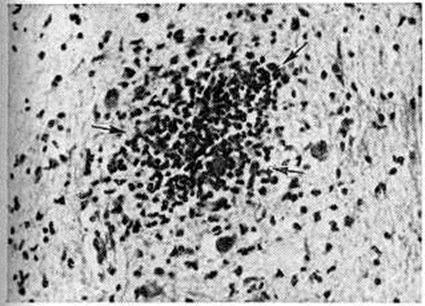

Географическое распространениеВ прошлом все войны сопровождались Сыпной тиф эпидемический Обычно от эпидемий Сыпной тиф эпидемический войска несли потери, намного превышающие боевые потери. Так, в русско-турецкую войну 1768— 1774 годы в русских войсках от Сыпной тиф эпидемический умерло около 44 тысяч человек, а от оружия погибло около 35 тысяч Наполеоновские войска разнесли Сыпной тиф эпидемический по всей Европе; в Германии в 1813—1814 годы Сыпной тиф эпидемический переболело 2—3 миллионов человек. Первая мировая война привела к высокому подъему заболеваемости Сыпной тиф эпидемический в ряде государств. Например, в Сербии в 1915 год погибло от Сыпной тиф эпидемический свыше 150 тысяч человек Во время Гражданской войны и иностранной интервенции и в последующие годы (1918— 1922) на территории СССР, по данным различных исследователей, Сыпной тиф эпидемический переболело от 7 до 20 миллионов человек Вторая мировая война также сопровождалась высокой заболеваемостью Сыпной тиф эпидемический во многих странах. Так, от эпидемий Сыпной тиф эпидемический в 1942—1944 годы пострадали страны Сев. Африки. Затем с войсками Сыпной тиф эпидемический проник в Италию (эпидемия в Неаполе), поразил Польшу, Германию, Румынию и другие, широко распространился в Иране и Ираке. Эпидемии Сыпной тиф эпидемический наблюдались и на территории СССР, временно оккупированной немецко-фашистскими войсками. Так, при освобождении от оккупации Великолукского района среди населения было выявлено 5205 больных, а на территории Невельского и соседнего районов — 5806. Заболеваемость Сыпной тиф эпидемический несколько повышалась и в тыловых районах СССР, что было связано с эвакуацией больших масс населения из западных районов страны на восток, со скученностью эвакуированных людей, живших нередко в не приспособленных для жилья помещениях (почти 70% больных приходилось на эвакуированных), однако болезнь не получила широкого распространения. ЭтиологияВозбудителем сыпного тифа является риккетсия Провачека — Rickettsia prowazekii da Rocha-Lima, 1916, относящаяся к роду Rickettsia семейство Rickettsiaceae. Риккетсии грамотрицательны, размером 0,3—0,6 × 0,8—2,0 микрометров (иногда до 4,0 микрометров). В отличие от других видов риккетсий (смотри полный свод знаний) у риккетсий Провачека при культивировании наблюдается полиморфизм — они принимают форму кокков и палочек (смотри полный свод знаний: рисунок 1 к статье Риккетсии). Риккетсии Провачека при окраске по Гимзе или по Здродовскому (модификация окраски Маккиавелло) красного цвета и хорошо видны в световом микроскопе; их ультраструктура (смотри полный свод знаний: рисунок 2 к статье Риккетсии) сходна с субмикроскопической организацией грамотрицательных бактерий. Размножаются риккетсии Провачека поперечным бинарным делением, время генерации при оптимальных условиях около 12 часов Риккетсии Провачека содержат протеины, углеводы, липиды, фосфолипиды, РНК, ДНК; в клеточной стенке обнаружены мурамовая и диаминопимелиновая кислоты, сахара, аминосахара, 17 аминокислот. Риккетсии Провачека, являясь внутриклеточными паразитами, располагаются в цитоплазме. Они хорошо размножаются в желточном мешке куриного эмбриона и на различных клеточных культурах; в культуре фибробластов куриного эмбриона образуют бляшки. Для риккетсий Провачека характерно наличие весьма лабильного токсина. Они чувствительны к действию высокой температуры, влажности, многих химический веществ. Вместе с тем они могут длительно сохраняться при низкой температуре в белковых субстратах, а также в высушенном виде. Особое значение имеет возможность длительного сохранения риккетсий в сухих фекалий зараженных вшей. Риккетсии Провачека чувствительны к действию ряда антибиотиков (левомицетина, тетрациклинов, эритромицина, рифампицина). Из лабораторный животных наиболее восприимчивы к риккетсиям Провачека хлопковые крысы и морские свинки (при всех способах заражения), белые мыши высокочувствительны к интраназальному заражению. ЭпидемиологияЕдинственным источником инфекции является больной человек, который остаётся источником заражения в течение 20— 21 дня, то есть последние два дня инкубации, весь лихорадочный период (до 17 дней) и первые два дня апирексии. До последних двух дней инкубационного периода и с третьего дня апирексии возбудителей Сыпной тиф эпидемический в крови больного, как правило, не обнаруживают. Переносчиком возбудителей инфекции при Сыпной тиф эпидемический служит платяная вошь (Pediculus vestimenti). Головная и лобковая вши (Pediculus capitis и Phthirus pubis) также могут переносить возбудителя, но их эпидемиологические роль по сравнению с платяной вошью незначительна (смотри полный свод знаний: Вши). Риккетсиями Сыпной тиф эпидемический вошь заражается при кровососании на больном; способной передавать возбудителя она становится лишь на 5—6-й день, реже — на 9 — 10-й день. В это время происходит накопление возбудителя и внедрение его в эпителий кишечной стенки вши. Однажды заразившись, вошь способна передавать возбудителя до конца своей жизни (живет до 45—46 дней). Своему потомству насекомые риккетсий не передают. Возбудители Сыпной тиф эпидемический, размножаясь и накапливаясь в большом количестве в эпителиальных клетках кишки вши, разрывают эти клетки и выделяются в просвет её кишечника. В других частях тела вши, в том числе в слюнных железах и в сосательном аппарате, риккетсий не содержится. Заражение человека Сыпной тиф эпидемический происходит следующим образом. Когда зараженная вошь прокалывает кожу человека и начинает сосать кровь, её кишечник постепенно наполняется кровью и одновременно происходит акт дефекации, при котором на поверхность кожи человека выделяются фекалии с большим количеством риккетсий. Укус вши сопровождается зудом. Человек, расчесывая место укуса, втирает заразный материал в образовавшиеся ссадины. Таким образом, возникновение и распространение Сыпной тиф эпидемический всегда связано с вшивостью (смотри полный свод знаний: Вши), сопровождающей ухудшение санитарный состояния тех или иных групп населения. Сыпной тиф эпидемический в прошлом нередко назывался военным, голодным, тюремным тифом. Сами эти названия говорят о том, что наибольшее распространение Сыпной тиф эпидемический получал во время войн, голода и других социальных потрясений, когда ухудшалось материальное положение народа, усиливалась миграция населения, наблюдался недостаток белья, мыла и тому подобное К Сыпной тиф эпидемический восприимчивы люди всех возрастов. В условиях распространения заболевания риску заражения наиболее подвержены работники транспорта, персонал бань, прачечных, дезинфекторы. В прошлом наблюдалась повышенная заболеваемость среди медперсонала. Внедрение в практику санобработки больных, дезинсекции вещей больного и санитарный транспорта снизило эту опасность. Выраженная сезонность Сыпной тиф эпидемический для средних широт (февраль — апрель) определяется увеличением контактов среди населения за счёт скученности в жилищах в холодное время года. ПатогенезРиккетсии Провачека, попадая в кровь человека, быстро проникают в клетки эндотелия кровеносных сосудов, где размножаются и выделяют эндотоксин. Под действием эндотоксина эндотелиальные клетки набухают, происходит их десквамация и разрушение. Риккетсии вновь поступают в кровь, часть из них гибнет, высвобождая эндотоксин, а остальные вновь проникают в клетки эндотелия сосудов. Такого рода процесс без видимых клинические, проявлений продолжается до тех пор, пока не наступит достаточное количественное насыщение организма риккетсиями и их эндотоксином. Последний обладает вазодилатационным эффектом, особенно в системе мелких сосудов — капилляров, прекапилляров, артериол, венул, в которых нарушается микроциркуляция (смотри полный свод знаний) вплоть до образования паралитической гиперемии и замедления тока крови. В результате этого создаются условия, способствующие развитию гиалиновых тромбов в местах паразитирования риккетсий, где произошла деструкция эндотелия сосудов, с последующим образованием в органах и тканях специфической гранулемы (смотри полный свод знаний). Такого рода изменения в сосудах выявляются с 6—8-го дня болезни практически во всех органах и тканях, но больше всего они выражены в головном мозге, в коже, конъюнктивах глазных яблок, надпочечниках, миокарде, почках. Известную роль в патогенезе Сыпной тиф эпидемический играет и аллергический компонент, но суть его пока не ясна. В процессе болезни наступает специфическая иммунная перестройка организма, ведущая в итоге к выздоровлению. Риккетсии могут обнаруживаться в органах и тканях в последние дни инкубации, во время всего лихорадочного периода и в первые дни апирексии. В организме больных возбудитель может длительно сохраняться и после клинического выздоровления, это явление ещё недостаточно изучено. Обратное развитие морфологический изменений начинается с 18—20-го дня от начала болезни и завершается в основном к концу 4-й недели, а иногда и позже. Патологическая анатомияПатологическая анатомия сыпного тифа изучена главным образом отечественными исследователями И. В. Давыдовским, А. П. Авцыным, Ш. И. Криницким и другие На коже можно обнаружить следы сыпи в виде неясно контурированных пятен и точек розового, коричневатого, красного цвета. Более стойким признаком является конъюнктивальная сыпь (смотри полный свод знаний: Киари — Авцына симптом). Отмечается серозный менингит (смотри полный свод знаний), полнокровие ткани головного мозга, значительное полнокровие и увеличение массы лёгких (в 2—4 раза), увеличение размеров селезенки в 2—3 раза. При гистологический исследовании обнаруживают характерное поражение кровеносных сосудов капиллярного типа, получившее название эндотромбоваскулита, с набуханием и деструкцией эндотелия, слущиванием его клеток в просвет сосуда и формированием пристеночного или обтурирующего тромба (смотри полный свод знаний). Эти изменения сопровождаются пролиферацией адвентициальных гистиоцитов, к которым примешиваются немногочисленные нейтрофилы и лимфоидные элементы, что наряду с очаговой гиперемией капилляров лежит в основе формирования сыпнотифозной розеолы. Углубление деструктивных изменений в сосудах, диапедез эритроцитов характеризуют превращение розеолы в сыпнотифозную петехию. Аналогичные изменения можно обнаружить в различных органах и системах. В головном мозге (смотри полный свод знаний) сыпнотифозные узелки, впервые описанные Л. В. Поповым (1875), обнаруживаются в варолиевом мосту (мост головного мозга), ножках мозга, коре головного мозга, базальных ядрах, таламусах (зрительных буграх), мозжечке, гипоталамусе, задней доле гипофиза. Как правило, сыпнотифозных узелков нет в белом веществе полушарий головного мозга. Сыпнотифозные узелки в ткани головного мозга построены из клеток микроглии, к к-рым, как правило, примешиваются сегментоядерные лейкоциты (рисунок 1). Важное диагностическое значение имеет скопление сыпнотифозных узелков в продолговатом мозге, в частности в области его нижних оливных ядер. Количество таких узелков в центральная нервная система зависит в основном от длительности лихорадочного периода. В случае смерти на 2—4-й неделе болезни их обнаруживают в 100%. У переболевших сыпнотифозные узелки регрессируют. Сохраняющиеся в более поздние периоды болезни гистологические изменения могут быть диагностическим признаком перенесённого в прошлом Сыпной тиф эпидемический В центральная нервная система отмечается, как правило, гиперемия и стазы (нередко с формированием гиалиновых тромбов в капиллярах серого вещества), периваскулярные (главным образом перивенозные) муфты из плазматических клеток, диффузная и очаговая пролиферация микроглии. Этот патогистологический комплекс (стазы, характерные сыпнотифозные узелки в сером веществе головного мозга, особенно в продолговатом мозге, муфты из плазматических клеток вокруг мелких вен, пролиферация макрофагов в мягкой оболочке головного мозга) даёт право считать, что каждый-случай Сыпной тиф эпидемический сопровождается энцефалитом (смотри полный свод знаний: Энцефалиты), выраженность которого широко варьирует. Следует отметить, что в противовес указанным сосудистым и интерстициальным изменениям в центральная нервная система тяжёлое альтеративное поражение нервных клеток и нервных волокон для типичного течения Сыпной тиф эпидемический не характерно.

В симпатической и в меньшей степени в парасимпатической нервной системе при Сыпной тиф эпидемический наблюдается интерстициальный ганглионит с образованием узелков и инфильтратов, пролиферацией капсульных клеток. Тяжёлые деструктивные ганглиониты и специфические невриты встречаются как исключение. Характерным признаком Сыпной тиф эпидемический является также и интерстициальный миокардит (смотри полный свод знаний), проявляющийся очаговой, реже диффузной инфильтрацией стромы миокарда плазматическими клетками в сочетании с большим или меньшим образованием сыпнотифозных узелков и слабыми изменениями кардиомиоцитов (рисунок 2). Отмечается также сыпнотифозный интерстициальный орхит (рисунок 3) и интерстициальный нефрит (смотри полный свод знаний), которые могут быть очаговыми и диффузными. Поражение почечных клубочков проявляется главным образом гиалиновым тромбозом (иногда с некрозом отдельных петель) и много реже очаговым гломерулонефритом (смотри полный свод знаний). При плохом уходе за полостью рта у больных, находящихся в прострации, наблюдаются гнойный паротит (смотри полный свод знаний) и воспаление подчелюстной железы (смотри полный свод знаний). Изредка встречаются небольшие инфильтраты, узелки и поражения сосудов желудка. Размеры печени увеличены, паренхима её мало изменена. Слизистая оболочка дыхательных путей обычно полнокровна. Закономерное увеличение массы лёгких и их вишнево-красный цвет обусловлены главным образом депонированием крови в малом круге кровообращения. Возможен отёк легких. В мышцах гортани при микроскопическом исследовании наблюдается специфический интерстициальный миозит. Относительно редки перихондрит (смотри полный свод знаний) и флегмона гортани (смотри полный свод знаний). Весьма частым осложнением являются пневмонии (обычно лобулярные, но изредка и лобарные). Своеобразную форму поражения более крупных сосудов представляют собой секторальные и реже циркулярные некрозы стенки артерий, сопровождающиеся явлениями плазморрагии (смотри полный свод знаний) и периваскулярными пролифератами. Они встречаются не ранее 3-й недели болезни, но могут наблюдаться и позже. Изредка они могут быть причиной тяжёлых локальных гемодинамических расстройств — размягчения мозга, сопровождающегося параличами (смотри полный свод знаний: Параличи, парезы), афазией (смотри полный свод знаний), клинические, картиной поперечного миелита (смотри полный свод знаний) и другие Эти же изменения в артериях сетчатки могут обусловить слепоту (смотри полный свод знаний). Очевидно, они же лежат в основе довольно редких внезапных кровоизлияний в мозг у реконвалесцентов. Эти поздние деструктивные изменения крупных артериальных стволов связывают с гиперсенсибилизацией организма. Интерстициальные инфильтраты могут наблюдаться в стенке аорты и в мышечной оболочке крупных вен. В эндокринных железах (гипофиз, надпочечники, щитовидная железа) можно обнаружить характерные сыпнотифозные узелки и очаговые инфильтраты. В селезёнке (смотри полный свод знаний) выявляют резко выраженную пролиферацию гистиоцитов и плазматических клеток, десквамацию их и более крупных макрофагальных элементов, а также скопление сегментоядерных лейкоцитов, умеренные отложения гемосидерина. В цитоплазме макрофагов и эндотелиальных клеток обнаруживают азурофильную зернистость, морфологически неотличимую от риккетсий. В костном мозге (смотри полный свод знаний) также отмечают пролиферацию базофильных гистиоцитов и реже образование специфических периваскулярных узелков. ИммунитетИнфекционных процесс при Сыпной тиф эпидемический сопровождается развитием стойкого и длительного иммунитета. Повторные заболевания редки. В работах П. Ф. Здродовского с сотрудники (1972) показано, что иммунитет при Сыпной тиф эпидемический возникает вскоре после заражения. В течение лихорадочного периода иммунитет нестерильный, то есть развивается в присутствии микроба, а после перенесенной болезни, по мнению многих исследователей, стерильный, сохраняющийся длительно (до 40 лет). Ряд исследователей — К. Н. Токаревич, Г. С. Мосинг, В. М. Колотов, Р. А. Пшеничный с сотрудники, Ш. Николау и Константинеско (N. Constantinesco) допускают возможность длительного переживания риккетсий в организме перенесшего Сыпной тиф эпидемический человека. С учётом этого К. Н. Токаревич и Г. С. Мосинг рассматривали возникший после Сыпной тиф эпидемический иммунитет как нестерильный. Возможна активная иммунизация вакциной, приготовленной из культуры риккетсий Провачека (смотри полный свод знаний: ниже Профилактика). Клиническая картинаИнкубационный период колеблется от 5 до 25 дней, чаще 10—12 дней. Различают легкое, среднетяжелое, тяжёлое и очень тяжёлое течение болезни. При наиболее типичном среднетяжелом течении Сыпной тиф эпидемический, наблюдаемом у 60—65% больных, болезнь начинается с повышения температуры, появления чувства жара, головокружения и головной боли, слабости, лёгкого познабливания и потливости, ломоты во всем теле, жажды и потери аппетита. Все эти признаки быстро нарастают, особенно головная боль, которая с первых дней становится мучительной. Появляются бессонница, боль в мышцах и суставах, обостряются восприятия, отмечаются раздражительность и беспокойство, иногда переходящее в состояние эйфории и возбуждения; возможно состояние заторможенности. Наблюдается выраженная гиперемия лица и конъюнктив — красные глаза на красном лице, гиперемия кожи шеи и верхней части туловища, лёгкая амимия, одутловатость лица, умеренный цианоз губ. Кожа на ощупь горячая, повышенной влажности; симптомы щипка и жгута положительные (смотри полный свод знаний: Кончаловского — Румпеля — Лееде симптом). Иногда бывает герпес на губах (смотри полный свод знаний: Герпес). С 3-го дня болезни можно обнаружить симптом Киари — Авцына — сыпь, располагающуюся на переходных складках конъюнктивы, то есть в области верхнего и нижнего сводов конъюнктивы, в виде единичных петехий, и симптом Розенберга — Винокурова — Лендорффа — энантема на мягком небе. Увеличивается селезенка, что выявляется перкуторно, а позднее и пальпаторно. Отмечаются умеренная одышка, умеренная тахикардия и приглушенность тонов сердца, гипотензия (смотри полный свод знаний). Может наблюдаться тремор языка (симптом Говорова — Годелье), нередко его девиация (отклонение), слабо выражен общий тремор (смотри полный свод знаний: Дрожание). Может наблюдаться бред (смотри полный свод знаний). На 4—6-й день болезни появляется характерная обильная розеолезнопетехиальная сыпь на коже боковых поверхностей груди, живота, сгибательных поверхностей верхних конечностей. Элементы сыпи редко бывают более 3 миллиметров в диаметре. Иногда сыпь появляется на ладонях и очень редко на лице. Розеолы и петехии при Сыпной тиф эпидемический кажутся плоскими и расплывчатыми, с неровными краями, так как располагаются обычно внутрикожно. При применении жгута точечные петехии (смотри полный свод знаний) на предплечье можно обнаружить уже с 3-го дня болезни. Иногда же розеолы возвышаются над кожей и исключительно редко превращаются в папулы. Элементы сыпи в течение 3— 5 дней имеют розовую, ярко-красную или несколько цианотичную окраску, затем розеолы бледнеют, а петехии становятся пигментированными. Через 7—9 дней от начала высыпания сыпь исчезает, оставляя на короткое время нечеткую пигментацию. Новых высыпаний при Сыпной тиф эпидемический, как правило, не бывает. Сыпь обычно обильная, редко бывает скудная и совсем редко отсутствует полностью. С появлением сыпи становятся более выраженными симптом щипка, конъюнктивальная сыпь и энантема, а также нарушения со стороны центральная нервная система Заметно понижается АД, усиливается тахикардия, отмечается глухость тонов сердца и расширение его границ; электрокардиографически регистрируются изменения, свидетельствующие о развитии миокардита. Нарастают слабость, головная боль и бессонница. Возможен, особенно по ночам, своеобразный сыпнотифозный делирий с галлюцинациями, бредом, характерны возбуждение беспокойство, суетливость. Иногда больные вскакивают с постели, пытаются бежать. Появляются симптомы поражения мозговых оболочек: слабо выраженные ригидность мышц затылка, симптомы Кернига — Брудзинского (смотри полный свод знаний: Кернига симптом, Менингит) при малоизмененной цереброспинальной жидкости (цитоз не превышает 100 клеток в 1 микролитров.). У многих больных становятся более четкими симптомы поражения черепно-мозговых нервов (черепных), в частности появляется сглаженность носогубных складок, могут наблюдаться снижение слуха, моно и полиневриты, умеренная гиперестезия кожи. Аппетит у больного снижен или совершенно отсутствует, беспокоит жажда. Язык сухой, обложен серо-грязным налетом, который часто принимает бурую окраску (фулигинозный язык); нередко на нем появляются трещины. Печень и селезёнка у большинства больных увеличены, отмечаются запоры, метеоризм. Может быть олигурия, или мочеиспускание происходит каплями при переполненном мочевом пузыре (парадоксальная ишурия). Изменения в моче незначительны, в виде лихорадочной альбуминурии. Температура к 5-му дню болезни достигает максимальных цифр (39—40° и выше) и держится до 12—14-го дня болезни с последующей нормализацией в течение 2—3 дней. Выздоровление начинается с понижения температуры и снижения интоксикации. Уменьшаются одутловатость лица и его гиперемия. Появляется интерес к окружающему, улучшаются сон и аппетит, усиливается мочеотделение. К 3— 5-му дню нормальной температуры размеры печени и селезенки приходят к норме. Яснее становятся тоны сердца и нормализуется АД. Однако у больных ещё отмечаются значительная адинамия и слабость, сохраняется гиперестезия кожи. Полное выздоровление наступает примерно через месяц после нормализации температуры. Легкое течение Сыпной тиф эпидемический обычно свойственно лицам молодого возраста. Явления общей интоксикации в этих случаях незначительны температура обычно не превышает 38°, сознание не изменено, иногда отмечается заторможенность. Бред наблюдается лишь у отдельных больных. Выражены головная боль и бессонница. Преобладает розеолезная сыпь, петехии немногочисленны. Печень и селезёнка увеличиваются примерно у трети больных. Более постоянны гиперемия и одутловатость лица, гиперемия конъюнктив, симптом Киари — Авцына, Говорова — Годелье. Лихорадочный период длится в среднем 9 дней. При тяжёлом течении Сыпной тиф эпидемический, которое встречается у 15—20% больных, наблюдается более интенсивное развитие сосудистых и мозговых симптомов вследствие выраженной интоксикации. Пульс частый, до 140 ударов в минуту, нередка аритмия, систолическое АД снижается до 70— 80 миллиметров. Тоны сердца глухие. Выражен акроцианоз. Наблюдается тахипноэ (смотри полный свод знаний), возможно нарушение ритма дыхания по типу биотовского (смотри полный свод знаний: Биотовское дыхание) или Чейна — Стокса (смотри полный свод знаний: Чейна — Стокса дыхание). Особенно значительны изменения в центральная нервная система Рано появляются психические расстройства, резкое возбуждение, делирий, быстро сменяющиеся заторможенностью. Выражены признаки поражения мозговых оболочек и дрожательный синдром вплоть до появления судорог (смотри полный свод знаний), наблюдаются нарушение глотания (смотри полный свод знаний: Дисфагия), дизартрия (смотри полный свод знаний). Температура достигает 41—42°. Сыпь преимущественно петехиальная с возможными значительными геморрагиями, что является грозным признаком. Выражена конъюнктивальная сыпь. Высшим проявлением тяжёлого течения Сыпной тиф эпидемический является глубокая кома (смотри полный свод знаний), в этом состоянии больные часто погибают. Как очень тяжёлая форма описывался так называемый молниеносный тиф — typhus siderans, когда вследствие тяжёлой интоксикации возникали изменения в надпочечниках и больные погибали в состоянии токсико-инфекционного шока (смотри полный свод знаний). Тяжелое и очень тяжёлое течение чаще всего наблюдается у пожилых людей. Встречаются атипичные формы болезни, при которых отдельные клинические, признаки Сыпной тиф эпидемический отсутствуют или нерезко выражены. У детей Сыпной тиф эпидемический протекает значительно легче и выздоровление наступает быстрее. Интоксикация, поражение сердечно-сосудистой системы и центральная нервная система у детей менее выражены, чем у взрослых. Болезнь начинается также менее остро. В начале заболевания обычно наблюдается умеренная общая интоксикация с несильной головной болью, катаральными явлениями, умеренными изменениями со стороны органов кровообращения, у части больных — дисфункция кишечника. Лихорадка бывает постоянной, ремиттирующей и неправильной; длительность лихорадочного периода не более 11— 13 дней. У большинства на 4—5-й день болезни появляется сыпь, преимущественно розеолезно-петехиальная; около 20% детей переносят Сыпной тиф эпидемический без сыпи. Потеря сознания, бред, галлюцинации, общее возбуждение не часты, а если и бывают, то выражены слабее, чем у взрослых. Печень и селезёнка увеличиваются не более чем у 40% больных. У большинства детей Сыпной тиф эпидемический протекает в лёгкой форме, реже — в форме средней тяжести и почти никогда — тяжело. Летальность при Сыпной тиф эпидемический у детей почти не регистрировалась. Период реконвалесценции протекает более благоприятно и быстрее, чем у взрослых. ОсложненияОсложнения Сыпной тиф эпидемический— коллапс (смотри полный свод знаний), пневмония (смотри полный свод знаний), миокардит (смотри полный свод знаний), тромбофлебиты (смотри полный свод знаний), тромбозы (смотри полный свод знаний), тромбоэмболии, нарушения мозгового кровообращения (смотри полный свод знаний: Инсульт, Тромбоэмболия), инфаркт миокарда (смотри полный свод знаний), позднее психозы, вторичная гнойная инфекция — отиты (смотри полный свод знаний), паротит (смотри полный свод знаний), пиелит (смотри полный свод знаний: Пиелонефрит) и другие У детей осложнения редки. ДиагнозДиагноз основывается на эпидемиологические данных (вшивость, контакт с больными Сыпной тиф эпидемический), характерной клинические, картине и данных лабораторный исследований, положительные результаты которых могут быть получены не ранее 6—7-го дня болезни. При Сыпной тиф эпидемический в разгар болезни в крови наблюдаются незначительное снижение количества эритроцитов, тромбоцитопения, умеренный лейкоцитоз с нейтрофилезом и палочкоядерным сдвигом (отмечается уже в начальном периоде), эозинопения, лимфопения, появление плазматических клеток, ускоренная РОЭ. Лабораторная диагностика осуществляется в основном путём определения в сыворотке крови антител к риккетсиям Провачека. Основные серологический реакции (смотри полный свод знаний: Серологические исследования) в лабораторный диагностике Сыпной тиф эпидемический: РСК — реакция связывания комплемента (смотри полный свод знаний), РИГА — реакция непрямой гемагглютинации (смотри полный свод знаний: Гемагглютинация), реакция агглютинации (смотри полный свод знаний: Агглютинация), метод иммунофлюоресценции (смотри полный свод знаний: Иммунофлюоресценция). РСК является одной из наиболее употребительных для распознавания сыпнотифозной инфекции как клинически выраженных случаев, так и стертых форм. С её помощью возможно также ретроспективное выявление инфекции, перенесенной в прошлом, так как комплементсвязывающие антитела к риккетсиям Провачека сохраняются до 10 лет и более. Комплементсвязывающие антитела обнаруживаются обычно с 5—7-го дня болезни у 50—60%, а с 10-го дня — у 100% больных сыпным тифом. Максимальные титры антител (1:320—1:5120) регистрируются на 2—3-й неделе заболевания. Диагностическим титром при однократном определении следует считать 1:160. Более достоверным является определение антител в динамике (через 5—7 дней после предыдущего исследования). Для ретроспективной диагностики Сыпной тиф эпидемический диагностическим титром является 1:10—1:20. Широкое распространение получила модификация РСК, предложенная Физе (P. Fiset), позволяющая ставить её с небольшими количествами ингредиентов. РНГА является высокочувствительной пробой. Для постановки этой реакции используют выпускаемый эритроцитарный диагностикум. РНГА даёт возможность диагностировать свежие случаи сыпного тифа, она положительна в большинстве случаев Сыпной тиф эпидемический; максимальные титры антител (1:6400—1:12800) регистрируются на 2—3-й неделе болезни, диагностический титр при однократном определении — 1:1000. Наиболее достоверным является определение антител в динамике. Реакция агглютинации является наиболее простой, но применяется редко, так как менее чувствительна, чем РСК и РНГА; диагностический титр реакции 1:160. Она высокочувствительна при применении антигена, полученного из риккетсий, выращенных во вшах (реакция Вейгля). Для обнаружения антител против риккетсий может быть использован непрямой люминесцентно-серологический метод. Дифференциальный диагноз. Сыпной тиф эпидемический дифференцируют с болезнью Брилла (смотри полный свод знаний: ниже), гриппом (смотри полный свод знаний), пневмонией (смотри полный свод знаний), менингитами (смотри полный свод знаний), геморрагическими лихорадками (смотри полный свод знаний), брюшным тифом (смотри полный свод знаний) и паратифами (смотри полный свод знаний), североазиатским клещевым риккетсиозом (смотри полный свод знаний), лекарственной болезнью (смотри полный свод знаний), трихинеллезом (смотри полный свод знаний), различными эритемами (смотри полный свод знаний: Эритема). Для дифференциальной диагностики Сыпной тиф эпидемический с болезнью Брилла важны данные анамнеза (для болезни Брилла — повторное заболевание); следует учитывать, что болезнь Брилла может возникнуть на фоне эпидемического благополучия. Дифференциальная диагностика Сыпной тиф эпидемический и болезни Брилла основана на известном в иммунологии положении о формировании различных классов иммуноглобулинов в результате первичного и повторного заболеваний и сопряженных с ними антигенных стимулов, которое в принципе применимо к этим заболеваниям. При Сыпной тиф эпидемический происходит формирование сначала IgM (198-антител), а затем IgG (78-антител), при болезни Брилла — быстрое формирование только IgG (78-антител). Поскольку IgM является более лабильным, его удаётся разрушить, например, применяя ряд редуцирующих веществ (2-меркаптоэтанол, цистеин и другие). Если при исследовании сыворотки крови больного такая обработка приводит к снижению титра антител в 4—8 раз и более, можно предположить, что в сыворотке крови находился в основном IgM, который затем разрушился; если титр сыворотки остался без изменений, можно предположить наличие IgG. Надо отметить, что при дифференцировании Сыпной тиф эпидемический и болезни Брилла основываться только на серологических методах не следует; необходимо учитывать весь комплекс клинические, и эпидемиологические показателей (например, заболевание Сыпной тиф эпидемический в прошлом). Чаще всего в начале заболевания Сыпной тиф эпидемический диагностируется как грипп. Однако грипп отличается от Сыпной тиф эпидемический более острым началом (больной называет не только день, но и час начала болезни), резкой слабостью в первый же день болезни, постоянной обильной потливостью, отсутствием одутловатости и амимии лица и симптома Говорова — Годелье. Головная боль локализуется обычно в области лба, надбровных дуг и височных областей, легко снимается анальгетиками, при надавливании на глазные яблоки и при движении ими возникает боль; для гриппа не характерны сыпь, увеличение печени и селезенки. При пневмонии отсутствуют сыпь, гепатолиенальный синдром, симптом Киари — Авцына, а также симптомы поражения ядер черепно-мозговых нервов. Менингиты различной этиологии отличаются от Сыпной тиф эпидемический наличием выраженного менингеального синдрома (ригидность мышц затылка, положительные симптомы Кернига и Брудзинского и другие). Решающим в диагностике может явиться анализ цереброспинальной жидкости (смотри полный свод знаний). При геморрагических лихорадках, особенно с почечным синдромом, более выражена гиперемия лица и конъюнктив, сыпь носит характер необильных точечных геморрагий, чаще на боковых поверхностях туловища и в подмышечных областях; обычны рвота и икота, боли в пояснице и животе; типичны жажда и олигурия, резко положительный симптом Пастернацкого (смотри полный свод знаний: Пастернацкого симптом). Характерны эритроцитоз, нормальная или ускоренная РОЭ, значительное повышение остаточного азота и мочевины крови, гематурия, альбуминурия, цилиндрурия. Для брюшного тифа и паратифов характерны бледность лица, адинамия и вялость. Язык утолщен, обложен, с отпечатками зубов по краям и на кончике. Часто отмечается брадикардия с дикротией пульса. Обычны метеоризм и урчание в правой подвздошной области, более позднее увеличение печени и селезенки. Сыпь скудная розеолезная, появляется не ранее 8-го дня болезни на груди, животе и боковых поверхностях туловища. В крови лейкопения с эозинопенией, палочкоядерный сдвиг с относительным лимфоцитозом, тромбоцитопенией. При североазиатском клещевом риккетсиозе, встречающемся в районах Сибири и Дальнего Востока, дифференциация основывается на наличии у большинства больных клещевым риккетсиозом первичного аффекта, представляющего собой плотный инфильтрат коричневого или бурого цвета чаще до 1,5 сантиметров в диаметре с возможным некрозом в центре; регионарного лимфаденита, который развивается почти одновременно с первичным аффектом; розеолезно-папулезной яркой сыпи по всему телу, появляющейся на 2— й день болезни. Аллергическая экзантема (смотри полный свод знаний: Сыпи), возникающая при лечении сульфаниламидами и антибиотиками больных различными остролихорадочными заболеваниями (грипп, пневмония и так далее), нередко смешивается с Сыпной тиф эпидемический, особенно при появлении сыпи на 4— й день от начала болезни. Элементы сыпи при этом чаще экссудативного характера, иногда розеолезно-папулезные, выступают над кожей, весьма обильны на всех участках тела, но больше на разгибательной поверхности суставов и имеют тенденцию к слиянию. Отмечается лимфаденопатия. Селезёнка обычно увеличена. Для клинические, картины трихинеллеза характерны отёк лица и век (одутловатка), головная боль и боль во всех группах мышц при движении и при их пальпации, умеренный конъюнктивит, иногда отёк конъюнктивы глазного яблока, болезненность при движении глаз. Сыпь обильная, может быть розеолезной, розеолезно-папулезной, уртикарной и даже петехиальной. Возможно нарастание сыпи. Типична гиперэозинофилия. В анамнезе — указание на употребление в пищу недостаточно термически обработанной свинины и нередко групповое заболевание. Различные эритемы — экссудативная и многоформная — отличаются от Сыпной тиф эпидемический тем, что сыпь при них покрывает все тело и лицо. Эритематозно-экссудативные элементы обычно крупных размеров и часто сливаются. Увеличиваются периферические лимфатических, узлы и селезенка. Выражены потливость, озноб, боли в суставах. Для многоформной эритемы характерна симметричность расположения сыпи. После её отцветания отмечается шелушение. ЛечениеНаиболее эффективными средствами являются препараты тетрациклинового ряда (тетрациклин, окситетрациклин, доксициклин — полусинтетическое производное окситетрациклина пролонгированного действия, сигмамицин, олететрин), а также левомицетин (хлороцид, хлорамфеникол). Тетрациклиновые препараты взрослым назначают по 0,3—0,4 грамм, а левомицетин — по 0,5 грамм 4 раза в сутки до 2-го дня нормальной температуры (детям антибиотики назначают соответственно возрасту). Тетрациклины (тетрациклин, окситетрациклин, сигмамицин и другие) можно вводить внутримышечно или внутривенно по 250 миллиграмм 2 раза в сутки при очень тяжёлом и тяжёлом течении болезни. Доксициклин назначают также внутрь в 1-е сутки по 0,1 грамм каждые 12 часов, в последующие дни — по 0,1 грамм 1 раз в сутки. При лечении антибиотиками температура нормализуется через 1½—2 суток При лечении тяжёлых и очень тяжёлых форм Сыпной тиф эпидемический проводится интенсивная терапия с использованием стероидных гормонов. Наряду с этим необходима и патогенетическая терапия, в частности применение сердечных и сосудистых, особенно прессорных, средств (камфоры, кордиамина, кофеина, норадреналина, эфедрина, гипертензина, мезатона), по показаниям — коргликона и строфантина. В случае выраженного возбуждения или делирия назначают бромиды, барбитураты, хлоралгидрат, аминазин, дроперидол, диазепам (седуксен). Лечение антибиотиками значительно сократило число осложнений, особенно связанных с вторичной микрофлорой. Возникающие осложнения другого рода требуют лечения в соответствии с их характером, например, антикоагулянтами при тромбозах и тромбоэмболиях. Все виды лечения должны сочетаться с соответствующей диетой в разгар болезни, полным покоем больного до 5—6-го дня нормальной температуры и тщательным уходом за ним. С 7—8-го дня нормальной температуры больным можно разрешить ходить. На 12-й день больного выписывают при условии нормального периода реконвалесценции. ПрогнозЛетальность в прошлом в отдельные эпидемии достигала 80%, в настоящее время благодаря антибиотикотерапии летальность резко снизилась и составляет менее 1%. ПрофилактикаРост материального и культурного уровня населения, а вслед за этим исчезновение вшивости исключили возможность циркуляции возбудителя и эпидемический характер распространения Сыпной тиф эпидемический в нашей стране. Встречающиеся отдельные случаи болезни Брилла требуют проведения неослабных профилактических мероприятий, поскольку эта форма болезни в эпидемическом отношении не отличается от Сыпной тиф эпидемический В первую очередь необходима повседневная профилактика вшивости. При наличии эпидемических показаний проводят регулярные осмотры детей в школах и дошкольных учреждениях, больных, поступающих в лечебный учреждения. При обнаружении вшивости проводят санитарную обработку (смотри полный свод знаний). Важное значение в профилактике вшивости, а следовательно, и Сыпной тиф эпидемический имеет санитарный просвещение, пропаганда мер по предупреждению вшивости и Сыпной тиф эпидемический В борьбе с возникшими заболеваниями ведущее место принадлежит раннему выявлению и изоляции больных Сыпной тиф эпидемический, ликвидации вшивости у них, а также изоляции лиц с подозрением на заболевание. Так как заразившаяся вошь становится способной передавать риккетсии людям лишь на 5—6-й день, выявление и госпитализация (изоляция) больного, его санобработка не позднее 5-го дня от начала болезни исключают возможность новых заболеваний, связанных с этим больным. В эпидемический очаге подворные обходы позволяют обеспечить раннее выявление лихорадящих больных, среди которых могут оказаться и больные Сыпной тиф эпидемический С этой же целью в течение 25 дней ведется медицинский наблюдение (с ежедневной термометрией) за лицами, общавшимися с больным Сыпной тиф эпидемический Вторым важным мероприятием в эпидемический очаге является ликвидация вшивости. Обязательной санобработке подвергается госпитализируемый больной, все лица, соприкасавшиеся с ним, постельные принадлежности и вещи, которыми пользовался больной, и помещение, где он жил. Специфическая профилактика имеет вспомогательное значение. Вейгль (R. Weigl, 1924) разработал метод изготовления вакцины из содержимого кишечника зараженных вшей, обработанного 0,5% раствором фенола. А. В. Пшеничнов и Б. М. Райхер в 1943 год использовали в качестве вакцины формалинизированную взвесь из растертых личинок вшей, зараженных риккетсиями Провачека. В 1940 год Кокс (Н. R. Сох) предложил приготовлять вакцину из риккетсий Провачека, накопленных в желточных мешочках куриных эмбрионов. М. К. Кронтовская с сотрудники и М. М. Маевский с сотрудники разработали и в 1941 год предложили метод изготовления лёгочной вакцины типа Дюрана — Жиру. Наилучшими продуцентами оказались белые мыши. Риккетсии накапливались в лёгких зараженных мышей; лёгкие соответствующим способом измельчали, обрабатывали формалином. Затем риккетсий извлекали центрифугированием. Вакцина Кронтовской — Маевского применялась во время Великой Отечественной войны как в войсках, так и среди населения. По мнению большинства специалистов, изучавших эффективность вакцины, она снижает заболеваемость и тяжесть течения болезни у привитых. При иммунизации населения заболеваемость у привитых была примерно в 2,5—3 раза ниже, чем среди непривитых. В настоящее время в СССР для специфической профилактики Сыпной тиф эпидемический изготовляется сухая химическая сыпнотифозная вакцина, представляющая собой очищенную концентрированную иммуногенную субстанцию поверхностного антигена риккетсий Провачека (смотри полный свод знаний: Иммунизация). Прививки этой вакциной проводятся лишь по эпидемический показаниям в случаях, когда трудно осуществимы обычные мероприятия по ликвидации очагов Сыпной тиф эпидемический Показаны также прививки медицинскому персоналу, работающему в условиях эпидемий Сыпной тиф эпидемический Особенности эпидемиологии и профилактики эпидемического сыпного тифа в войскахВ прошлом Сыпной тиф эпидемический именовали военным тифом, так как эпидемии Сыпной тиф эпидемический всегда сопровождали войны, производили опустошения среди населения и поражали войска, выводя из строя целые соединения и армии. Массивные эпидемии его отмечены в войсках ряда стран Европы в 18—19 веков Высокая заболеваемость Сыпной тиф эпидемический имела место и в русской армии. Так, армия Кутузова в период преследования наполеоновских войск в 1812 год понесла от Сыпной тиф эпидемический большие потери. В Крымскую войну, по данным Т. Е. Болдырева, с ноября 1853 год по ноябрь 1855 год только в южной (русской) армии заболело тифами 29 411 человек, из них умерло 6929 человек В русско-турецкую войну 1877 — 1878 годы в Дунайской и Кавказской армиях заболело 36 656 человек, из них умерло 12 071 человек Высокой была заболеваемость Сыпной тиф эпидемический и в период русско-японской войны 1904— 1905 годы (5,0—5,3 на 1000 человек личного состава), а в годы гражданской войны она достигла 130,67 на 1000 человек личного состава (1919). В послевоенные годы мирного строительства заболеваемость Сыпной тиф эпидемический в Красной Армии практически была ликвидирована. В 1941—1945 годы на территории, оккупированной немецко-фашистской армией, Сыпной тиф эпидемический получил широкое распространение среди местного населения. Немецко-фашистское командование не только не проводило никаких мер борьбы с Сыпной тиф эпидемический, но умышленно концентрировало больных Сыпной тиф эпидемический в населенных пунктах на пути предполагаемого наступления советских войск, создавая угрозу заноса и распространения Сыпной тиф эпидемический среди наших войск. Благодаря чётко организованным противоэпидемическим мероприятиям (смотри полный свод знаний: Система противоэпидемического обеспечения Вооруженных Сил) в войсках удалось сохранить эпидемическое благополучие, в то время как армия оккупантов несла значительные потери от Сыпной тиф эпидемический Вследствие специфических условий размещения личного состава войск в действующей армии (скученность, возможные временные перебои в банно-прачечном обслуживании и другие) создаются условия для распространения занесенного в войска Сыпной тиф эпидемический Поэтому в системе противоэпидемического обеспечения войск, как в мирное, так и в военное время, предусмотрен комплекс профилактических мероприятий, направленных на недопущение заноса Сыпной тиф эпидемический в войска и предупреждение вшивости: соблюдение уставных требований личной и общественной гигиены; еженедельное мытье в бане со сменой белья; регулярные медосмотры личного состава, изоляция и полная санитарная обработка (смотри полный свод знаний) лиц с выявленной вшивостью, а также контактировавших с ними; медицинский контроль за прибывающим пополнением и возвращающимися из командировок, отпусков, их санобработка, а при необходимости карантинизация на 14 дней (смотри полный свод знаний: Карантин, карантинизация); контроль за санитарный состоянием личного состава и транспортных средств при перевозках по железнодорожные, водным и автомобильным путям сообщения, своевременная санобработка в пути следования; в военное время — недопущение контакта с местным населением в случае размещения или ведения боевых действий на территории, неблагополучной по Сыпной тиф эпидемический Своевременная информация об эпидемический обстановке достигается непрерывным проведением санитарно-эпидемиологический разведки (смотри полный свод знаний: Медицинская разведка, Санитарно-эпидемиологическое наблюдение). При явной угрозе заноса Сыпной тиф эпидемический в войска личный состав подвергается иммунизации. При выявлении в части больного Сыпной тиф эпидемический его следует немедленно изолировать, провести санобработку, а также дезинсекцию обмундирования, белья, постельных принадлежностей больного и транспорта, на котором он был доставлен (смотри полный свод знаний: Дезинсекция). Больных в военное время эвакуируют в инфекционные госпиталь (смотри полный свод знаний: Инфекционный полевой подвижной госпиталь). Эвакуацию следует осуществлять на санитарный транспорте, который после доставки больного в госпиталь должен обеззараживаться. Личный состав, имевший контакт с больным, обязан пройти полную санобработку, за ним устанавливается наблюдение с ежедневной термометрией. Для установления источника заражения с целью принятия радикальных мер для прекращения дальнейшего распространения Сыпной тиф эпидемический необходимо проводить санитарно-эпидемический обследование (смотри полный свод знаний: Эпидемиологическое обследование). Болезнь БриллаБолезнь Брилла (синонимы: повторный сыпной тиф, рецидивный сыпной тиф, болезнь Брилла — Цинссера) — острая циклическая инфекционная болезнь, проявляющаяся через многие годы у лиц, переболевших Сыпной тиф эпидемический Она характеризуется спорадичностью заболеваний при отсутствии вшивости, более легким, чем при Сыпной тиф эпидемический, течением и типичным клиническим симптомокомплексом. Впервые острую инфекционные болезнь неясной природы, напоминающую сыпной тиф, наблюдал Брилл (N. Е. Brill) в 1898 и 1910 годы в Нью-Йорке. Позже её описали и другие исследователи, которые особо подчеркивали отсутствие связи с источником инфекции и вшивостью среди лиц из окружения больного. В 1934 год Г. Цинссер выдвинул гипотезу, что данная болезнь является рецидивом перенесённого многие годы назад Сыпной тиф эпидемический вследствие активизации риккетсий Провачека, сохранившихся в латентном состоянии в тканях организма. Позже Прайс (W. Н. Price, 1955) выделил два штамма риккетсий Провачека из лимфатических, узлов двух умерших, перенёсших Сыпной тиф эпидемический за 20 лет до смерти. В последующем Ш. Николау и Константинеско (N. Constantinesco, 1965) сообщили о выделении более 20 штаммов риккетсий Провачека от лиц, страдавших различными сердечно-сосудистыми болезнями и переболевших ранее Сыпной тиф эпидемический Гипотеза эндогенного происхождения болезни Брилла была поддержана в нашей стране П. Ф. Здродовским, Г. С. Мосингом, К. Н. Токаревичем и другие Вместе с тем Л. В. Громашевский, М. Н. Соловьев, И. И. Елкин и другие считали, что случаи повторного заболевания Сыпной тиф эпидемический связаны с реинфекцией лиц, перенёсших Сыпной тиф эпидемический в прошлом, но утративших иммунитет к нему. В условиях завшивленности больные болезнью Брилла могут явиться источником заболеваний Сыпной тиф эпидемический Патогенез и патологическая анатомия при болезни Брилла те же, что и при Сыпной тиф эпидемический, но относительно менее выражена риккетсиозная интоксикация. Развивается стойкий и длительный иммунитет. Болезнь Брилла начинается остро, с чувства жара, иногда с легким познабливанием, слабости, головной боли, бессонницы, потери аппетита, повышения температуры. Эти явления прогрессируют в течение первых 2—3 дней. В первые дни головная боль почти всегда сильная, бессонница стойкая. К 4—5-му дню болезни температура достигает 38—40°. Средняя длительность лихорадочного периода 8—10 дней, снижение температуры происходит обычно в течение двух суток. С первых дней болезни обычно на фоне лихорадочного возбуждения выявляются гиперемия и одутловатость лица, гиперемия конъюнктив, блеск глаз, гиперемия кожи шеи и верхней трети туловища, умеренный цианоз губ, положительный симптом щипка, элементы конъюнктивальной сыпи (симптом Киари — Авцына), энантемы на слегка гиперемированной слизистой оболочке мягкого неба (симптом Розенберга — Винокурова — Лендорффа). На 4—6-й, а иногда на 7—8-й день болезни у большинства больных появляется обильная розеолезно-петехиальная сыпь с локализацией на груди, боковых поверхностях туловища, спине, сгибательных поверхностях рук. Сохраняется она в течение 5—7 дней, после чего бесследно исчезает. Примерно у трети больных наблюдается только розеолезная или розеолезно-папулезная сыпь, иногда сыпь может и отсутствовать. Возможна одышка, но обычно дыхание соответствует температуре, как и пульс. Тахикардия отмечается не более чем у 25% больных, нередко имеет место и брадикардия. Более постоянна гипотензия. Тоны сердца приглушены, иногда значительно, может выслушиваться систолический шум. Электрокардиографически выявляются признаки диффузного миокардита. Язык обложенный, сухой. Печень и селезёнка умеренно увеличены у большинства больных. Возможна олигурия, незначительная альбуминурия и изредка парадоксальная ишурия. Многообразна характерная симптоматика, связанная с поражением центральная нервная система Головная боль и бессонница столь же мучительны, как и при классическом Сыпной тиф эпидемический Почти так же выражена эйфория. Серьезные психические нарушения наблюдаются редко, но возбужденность или заторможенность, умеренный сноподобный делирий, иногда деперсонализация, двигательное возбуждение в той или иной степени отмечаются часто. Возможен общий тремор (дрожание губ и конечностей, особенно пальцев рук, незначительная дизартрия), лёгкая сглаженность носогубных складок, девиация языка, симптом Говорова — Годелье, симптомы менингизма. Один или несколько из этих симптомов, чаще симптом Говорова — Годелье и гиперестезия кожи, появляются уже на 3—4-й день болезни. Нередко отмечается неврит слухового нерва. Обычно болезнь бывает средней тяжести или протекает легко; тяжёлое течение встречается редко, как правило, у пожилых лиц. Изменения крови не характерны. Реконвалесценция начинается с 10—12-го дня болезни и протекает быстрее, чем при Сыпной тиф эпидемический Сердечнососудистая деятельность восстанавливается к 5—7-му дню нормальной температуры, и лишь у некоторых больных в более поздние сроки наблюдается постинфекционный миокардит. Восстановление функций центральной нервной системы наступает к 15—17-му дню нормальной температуры. Размеры печени и селезенки нормализуются к 3—4-му дню периода реконвалесценции. Выписка больных допускается после нормализации температуры на 11 — 12-й день. Осложнения, диагноз, дифференциальный диагноз и лечение те же, что и при Сыпной тиф эпидемический Прогноз обычно благоприятный. Редкие летальные исходы обусловлены развитием тромбозов, тромбоэмболий, коллапса, инфаркта миокарда, пневмонии. При возникновении болезни Брилла проводятся мероприятия, направленные на предупреждение распространения эпидемического сыпного тифа. Смотри полный свод знаний: Риккетсиозы.